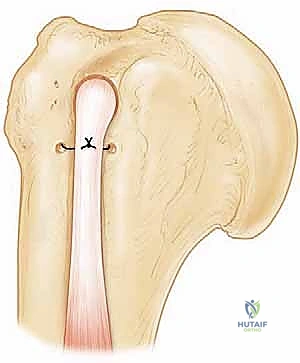

5. الخطوة الثالثة: إصلاح تمزق العضلة تحت الكتف (Subscapularis Repair)

هذه هي الخطوة الأساسية والأكثر دقة:

* تنظيف وتجهيز العظم: يتم تنظيف منطقة ارتكاز الوتر على عظم العضد (الحديبة الصغيرة) لإزالة الأنسجة الندبية وكشف العظم الحي، مما يحفز تدفق الدم ويساعد على التئام الوتر بالعظم لاحقاً.

* تحرير الوتر: إذا كان الوتر متراجعاً ومتقلصاً للداخل، يقوم الجراح بتحريره بلطف من الأنسجة المحيطة لضمان عودته إلى مكانه الطبيعي دون شد مفرط.

* وضع الخطاطيف (Suture Anchors): يقوم الدكتور هطيف بزرع خطاطيف جراحية دقيقة (مسامير صغيرة جداً محملة بخيوط طبية فائقة القوة) في العظم.

* خياطة الوتر: يتم تمرير هذه الخيوط عبر نسيج الوتر الممزق باستخدام أدوات دقيقة.

* العقد والتثبيت: يتم عقد الخيوط بإحكام لسحب الوتر وربطه بقوة بسطح العظم، مما يعيد التشريح الطبيعي للكتف.